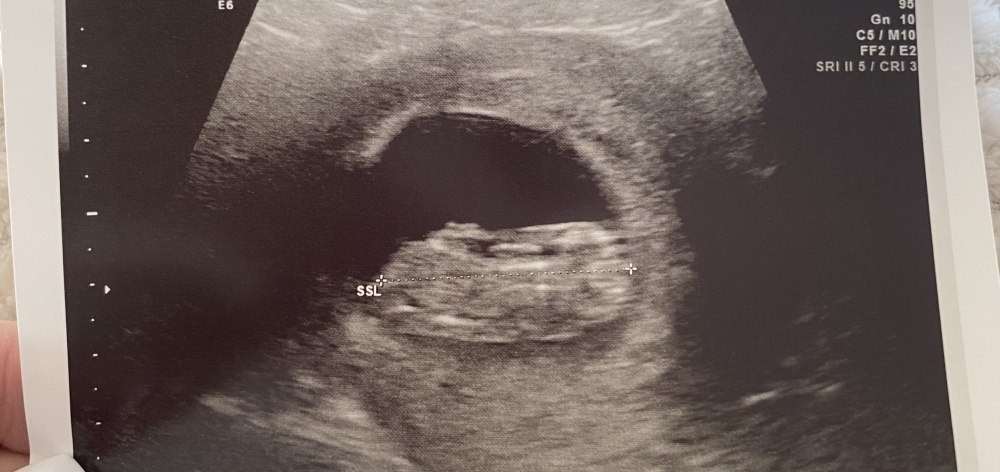

Kennt sich hier eventuell jemand mit der Nub Theorie aus & könnte seinen Tipp abgeben?

Bin aktuell in der 11. SSW & das Bild ist von Gestern.

Kennt sich hier eventuell jemand mit der Nub Theorie aus & könnte seinen Tipp abgeben?

Bin aktuell in der 11. SSW & das Bild ist von Gestern.